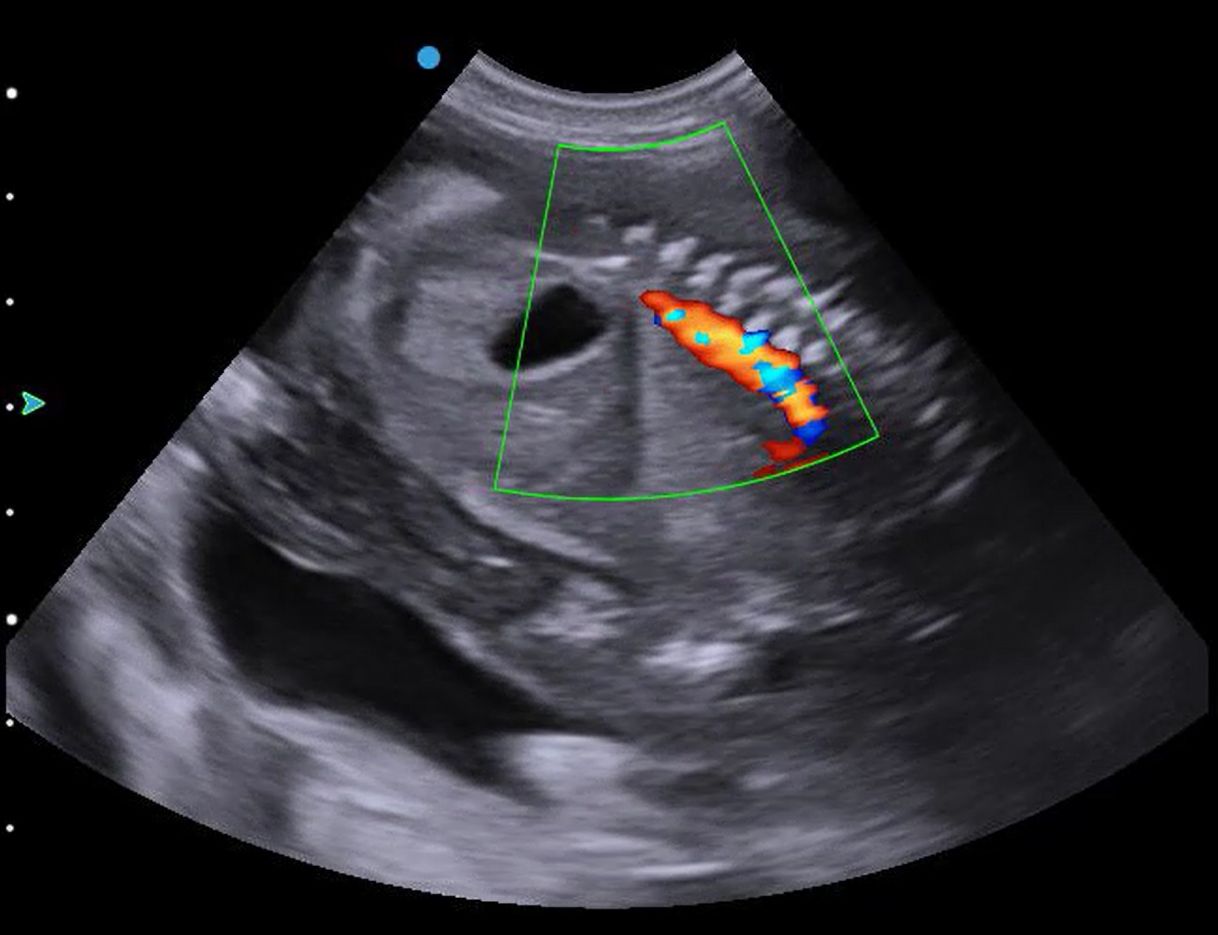

During this repeat pregnancy scan, I looked for heartbeats and movement from each puppy. All look very healthy, and I was able to use my Doppler to examine blood flow